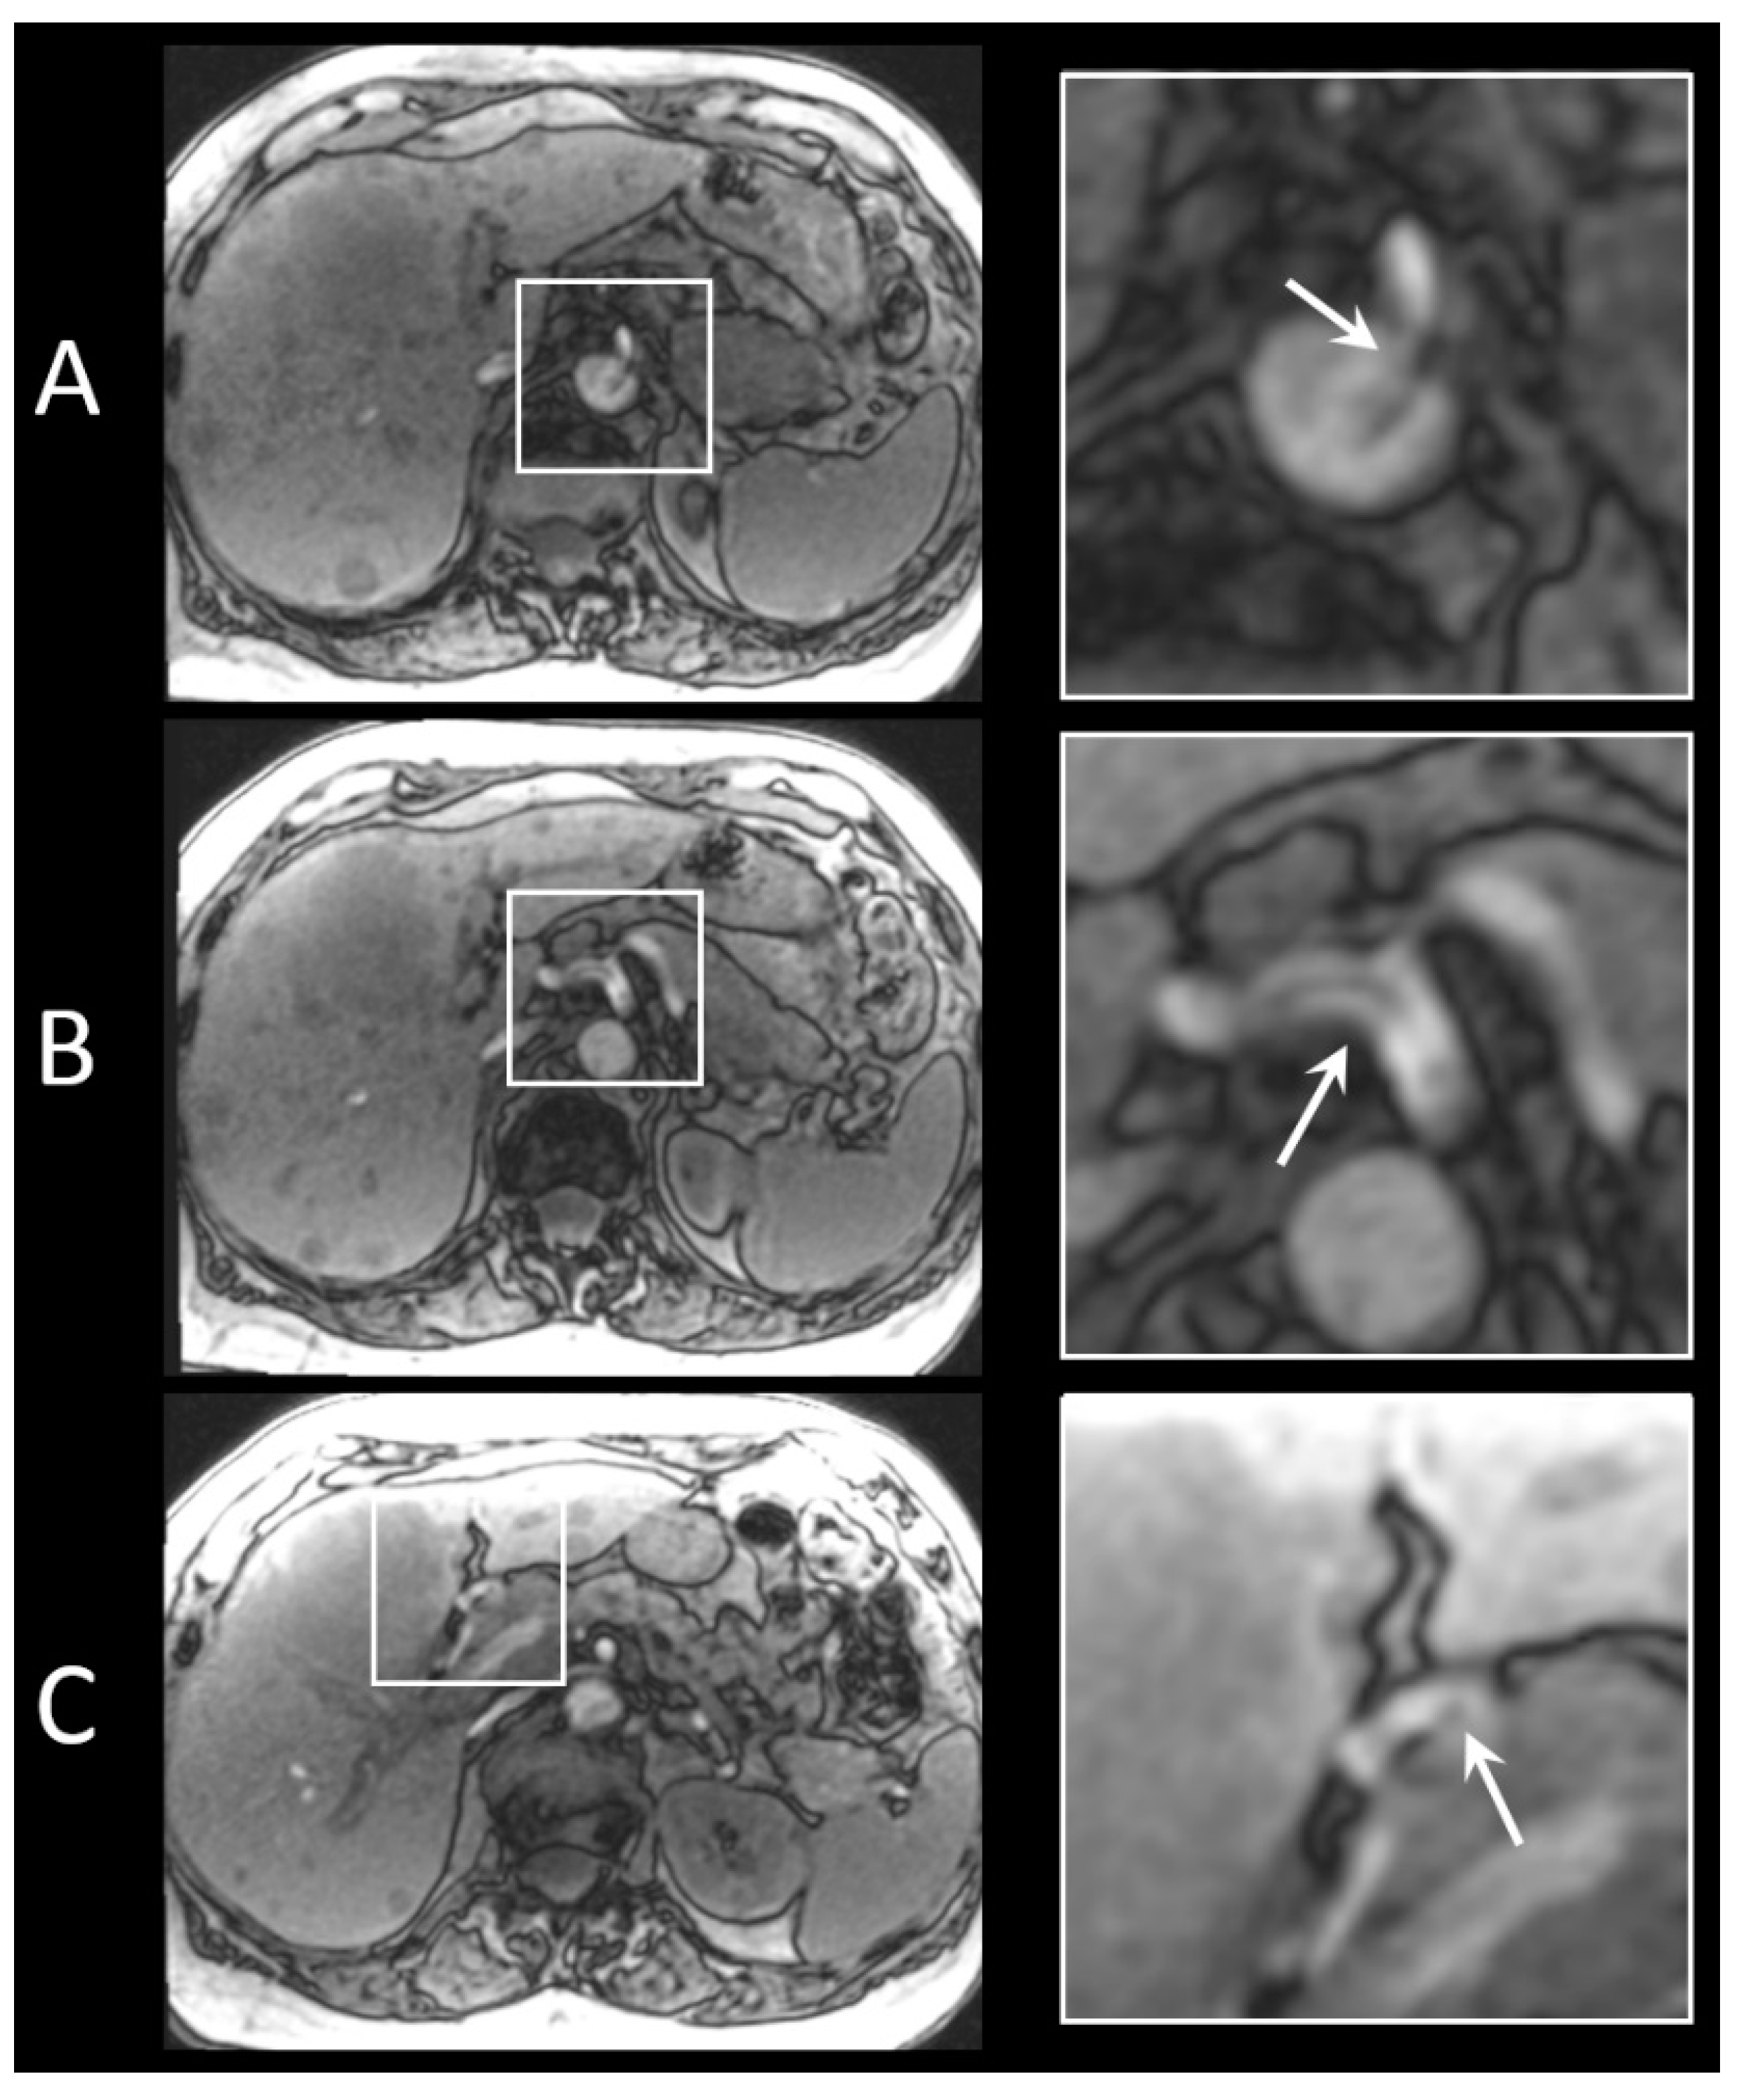

2.2.2. In Vivo Procedure

3.5. In Vivo Visibility during Holmium-166 SIRT

4. Discussion